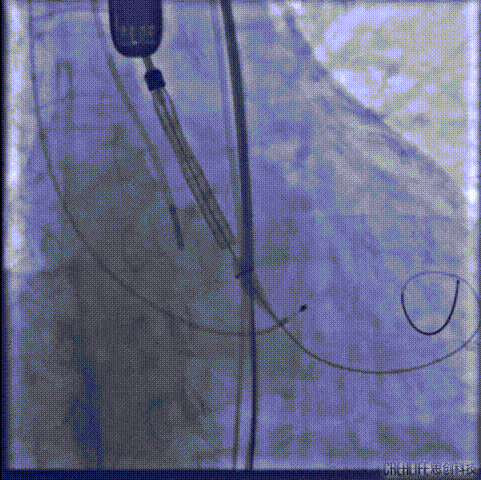

TaurusOne®释放过程:

瓣膜定位